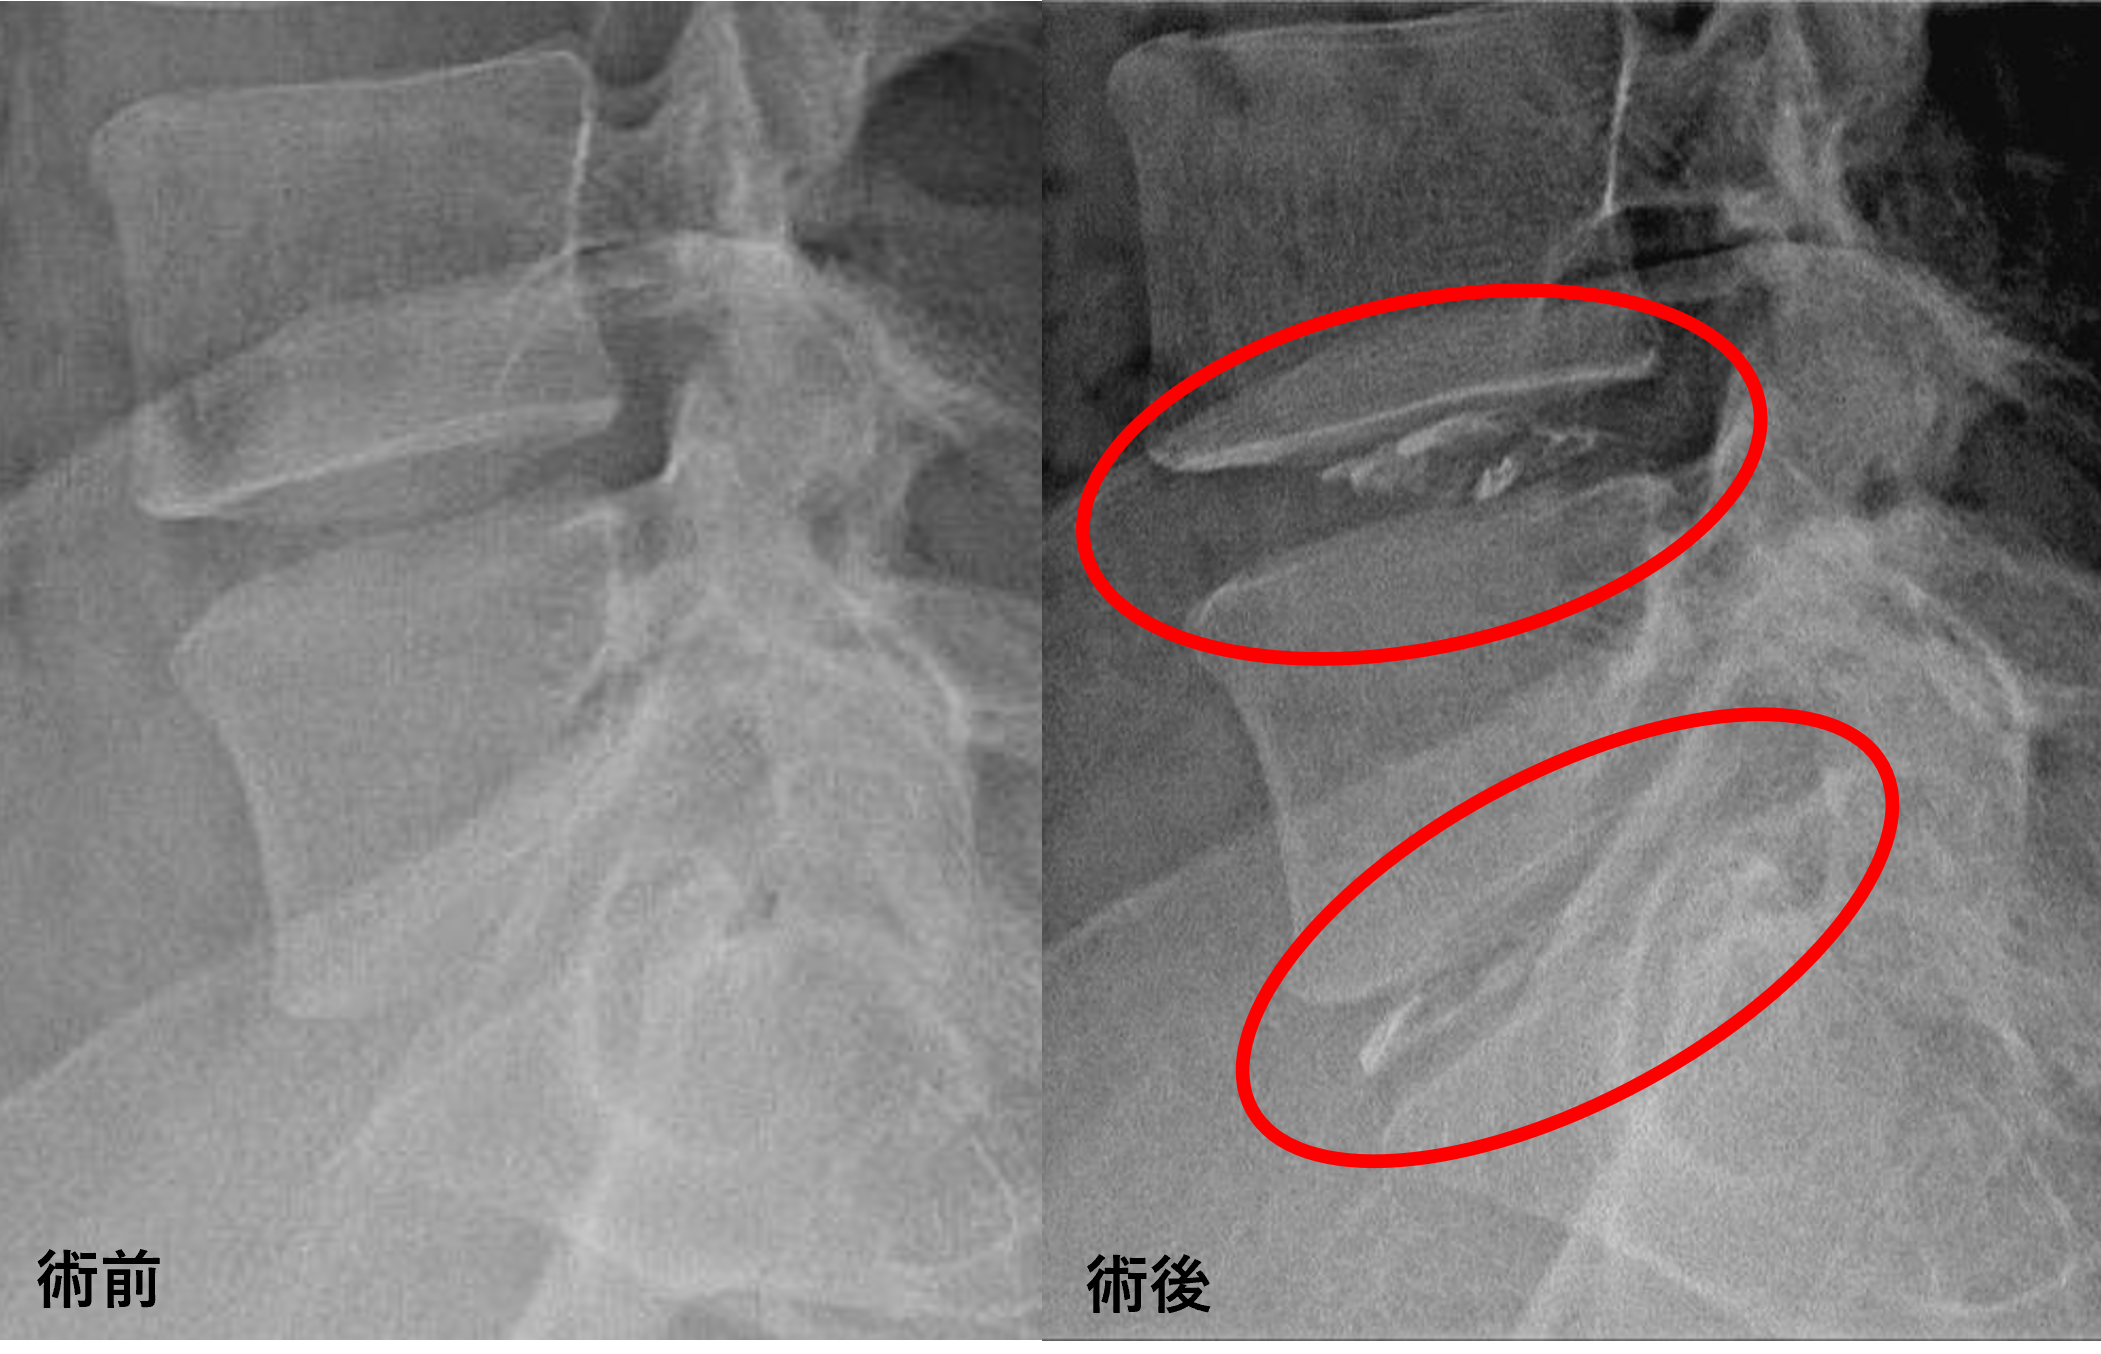

画像及び所見について

- L4/5、5/s – 椎間板変性、椎間板ヘルニア、繊維輪断裂

以上のことが画像上認められました。

L4/5、5/sの椎間板所見による脊柱管の圧排が、症状の原因の可能性が高い。

患者様と相談の元、L4/5、5/sにセルゲル法を施行